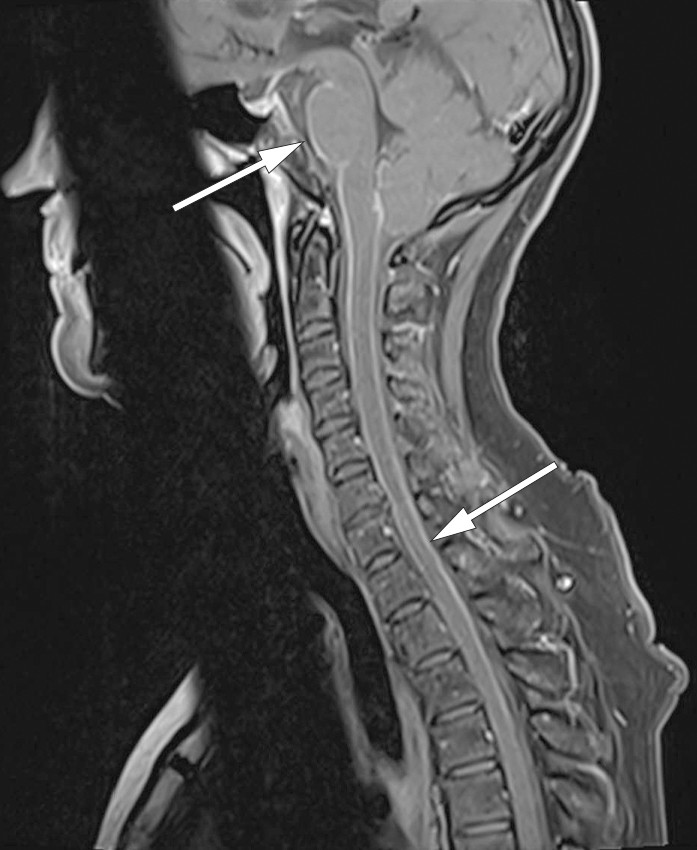

Man gjorde derfor kontrastforsterket MR-undersøkelse av medulla, som viste nytilkomne intramedullære forandringer forenlige med myelitt og meningitt (figur 2 og 3). På dette tidspunktet hadde det tilkommet diskrete trunkale sensoriske forstyrrelser og lett hyperrefleksi i underekstremitetene.

Billedfunn av myelitt og meningitt kombinert med cerebrospinalvæskefunnene gjorde at man konkluderte med nevroborreliose. Cerebral vaskulitt i mindre kar i bakre kretsløp sekundært til nevroborreliose ble vurdert som årsak til hjerneinfarktene.